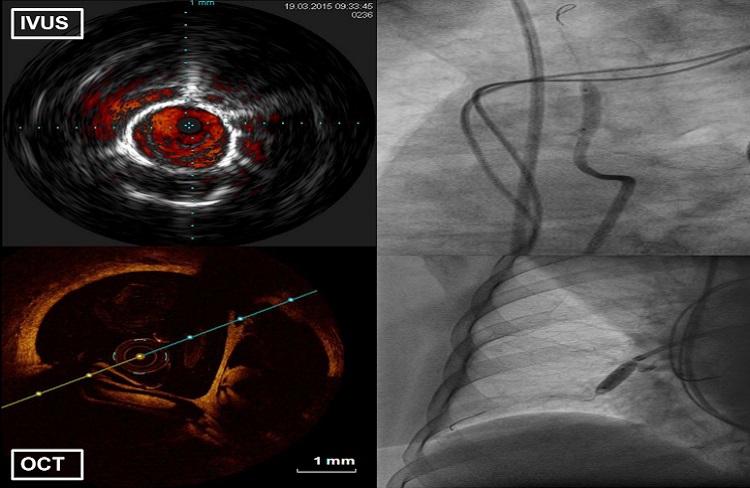

- cyfrowy system do obrazowania wewnątrzwieńcowego IVUS Volcano Philips;

- systemy do oceny czynnościowej zwężeń w tętnicach wieńcowych i płucnych – FFR/iFR Volcano Philips, Acist RXi Bracco Iamging, Quantien Abott ) do zabiegów kardiologicznych oraz angiologicznych;

- diagnostykę zmian granicznych stwierdzonych w trakcie koronarografii (zwężenia 40-70%), przy pomocy oceny czynnościowej zwężeń (FFR) oraz oceny morfologicznej (ultrasonografii wewnątrzwieńcowej -IVUS);

- Roik M, Wretowski D, Labyk A, Kostrubiec M, Irzyk K, Dzikowska-Diduch O, Lichodziejewska B, Ciurzynski M, Kurnicka K, Golebiowski M and Pruszczyk P. Refined balloon pulmonary angioplasty driven by combined assessment of intra-arterial anatomy and physiology–Multimodal approach to treated lesions in patients with non-operable distal chronic thromboembolic pulmonary hypertension–Technique, safety and efficacy of 50 consecutive angioplasties. Int J Cardiol. 2016;203:228-35.

- Rzadkim odległym powikłaniem ostrej zatorowości płucnej jest nadciśnienie płucne o etologii zakrzepowo zatorowej (chronic thromboembolic pulmonary hypertension, CTEPH). W Klinice prowadzimy pełną diagnostykę chorych z podejrzeniem CTEPH, a tod 2014 wykonujemy plastyki balonowe tętnic płucnych u chorych z potwierdzonym CTEPH nie zakwalifikowanych do leczenia kardiochirurgicznego. Zabiegi wykonywane są z zastosowaniem nowoczesnych metod wewnątrznaczyniowego obrazowania (FFR/IVUS/OCT) co zwiększa bezpieczeństwo i skuteczność tych zabiegów.

- Plastyki balonowe tętnic płucnych u chorych z potwierdzonym zakrzepowo zatorowym nadciśnieniem płucnym z zastosowaniem nowoczesnych metod wewnątrznaczyniowego obrazowania (FFR/IVUS/OCT), co zwiększa bezpieczeństwo i skuteczność tych zabiegów.